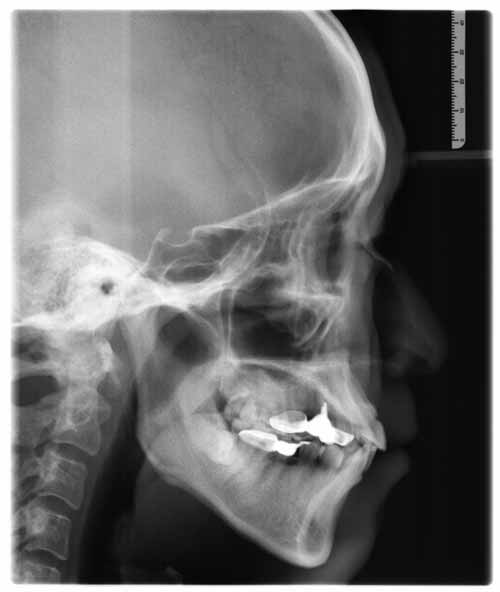

临床诊断:经过数字化全景机的拍片检查,顾客属于牙性地包天,且存在上牙拥挤错位,侧貌突,下颌前倾,X片显示根尖无异常。由于顾客的职业特殊性,可选择天使隐形正畸,在旁人无法擦觉的情况下完成整个矫正过程,顾客对此方案表示愿意接受,并十分期待矫正后的效果。

全景机侧位片